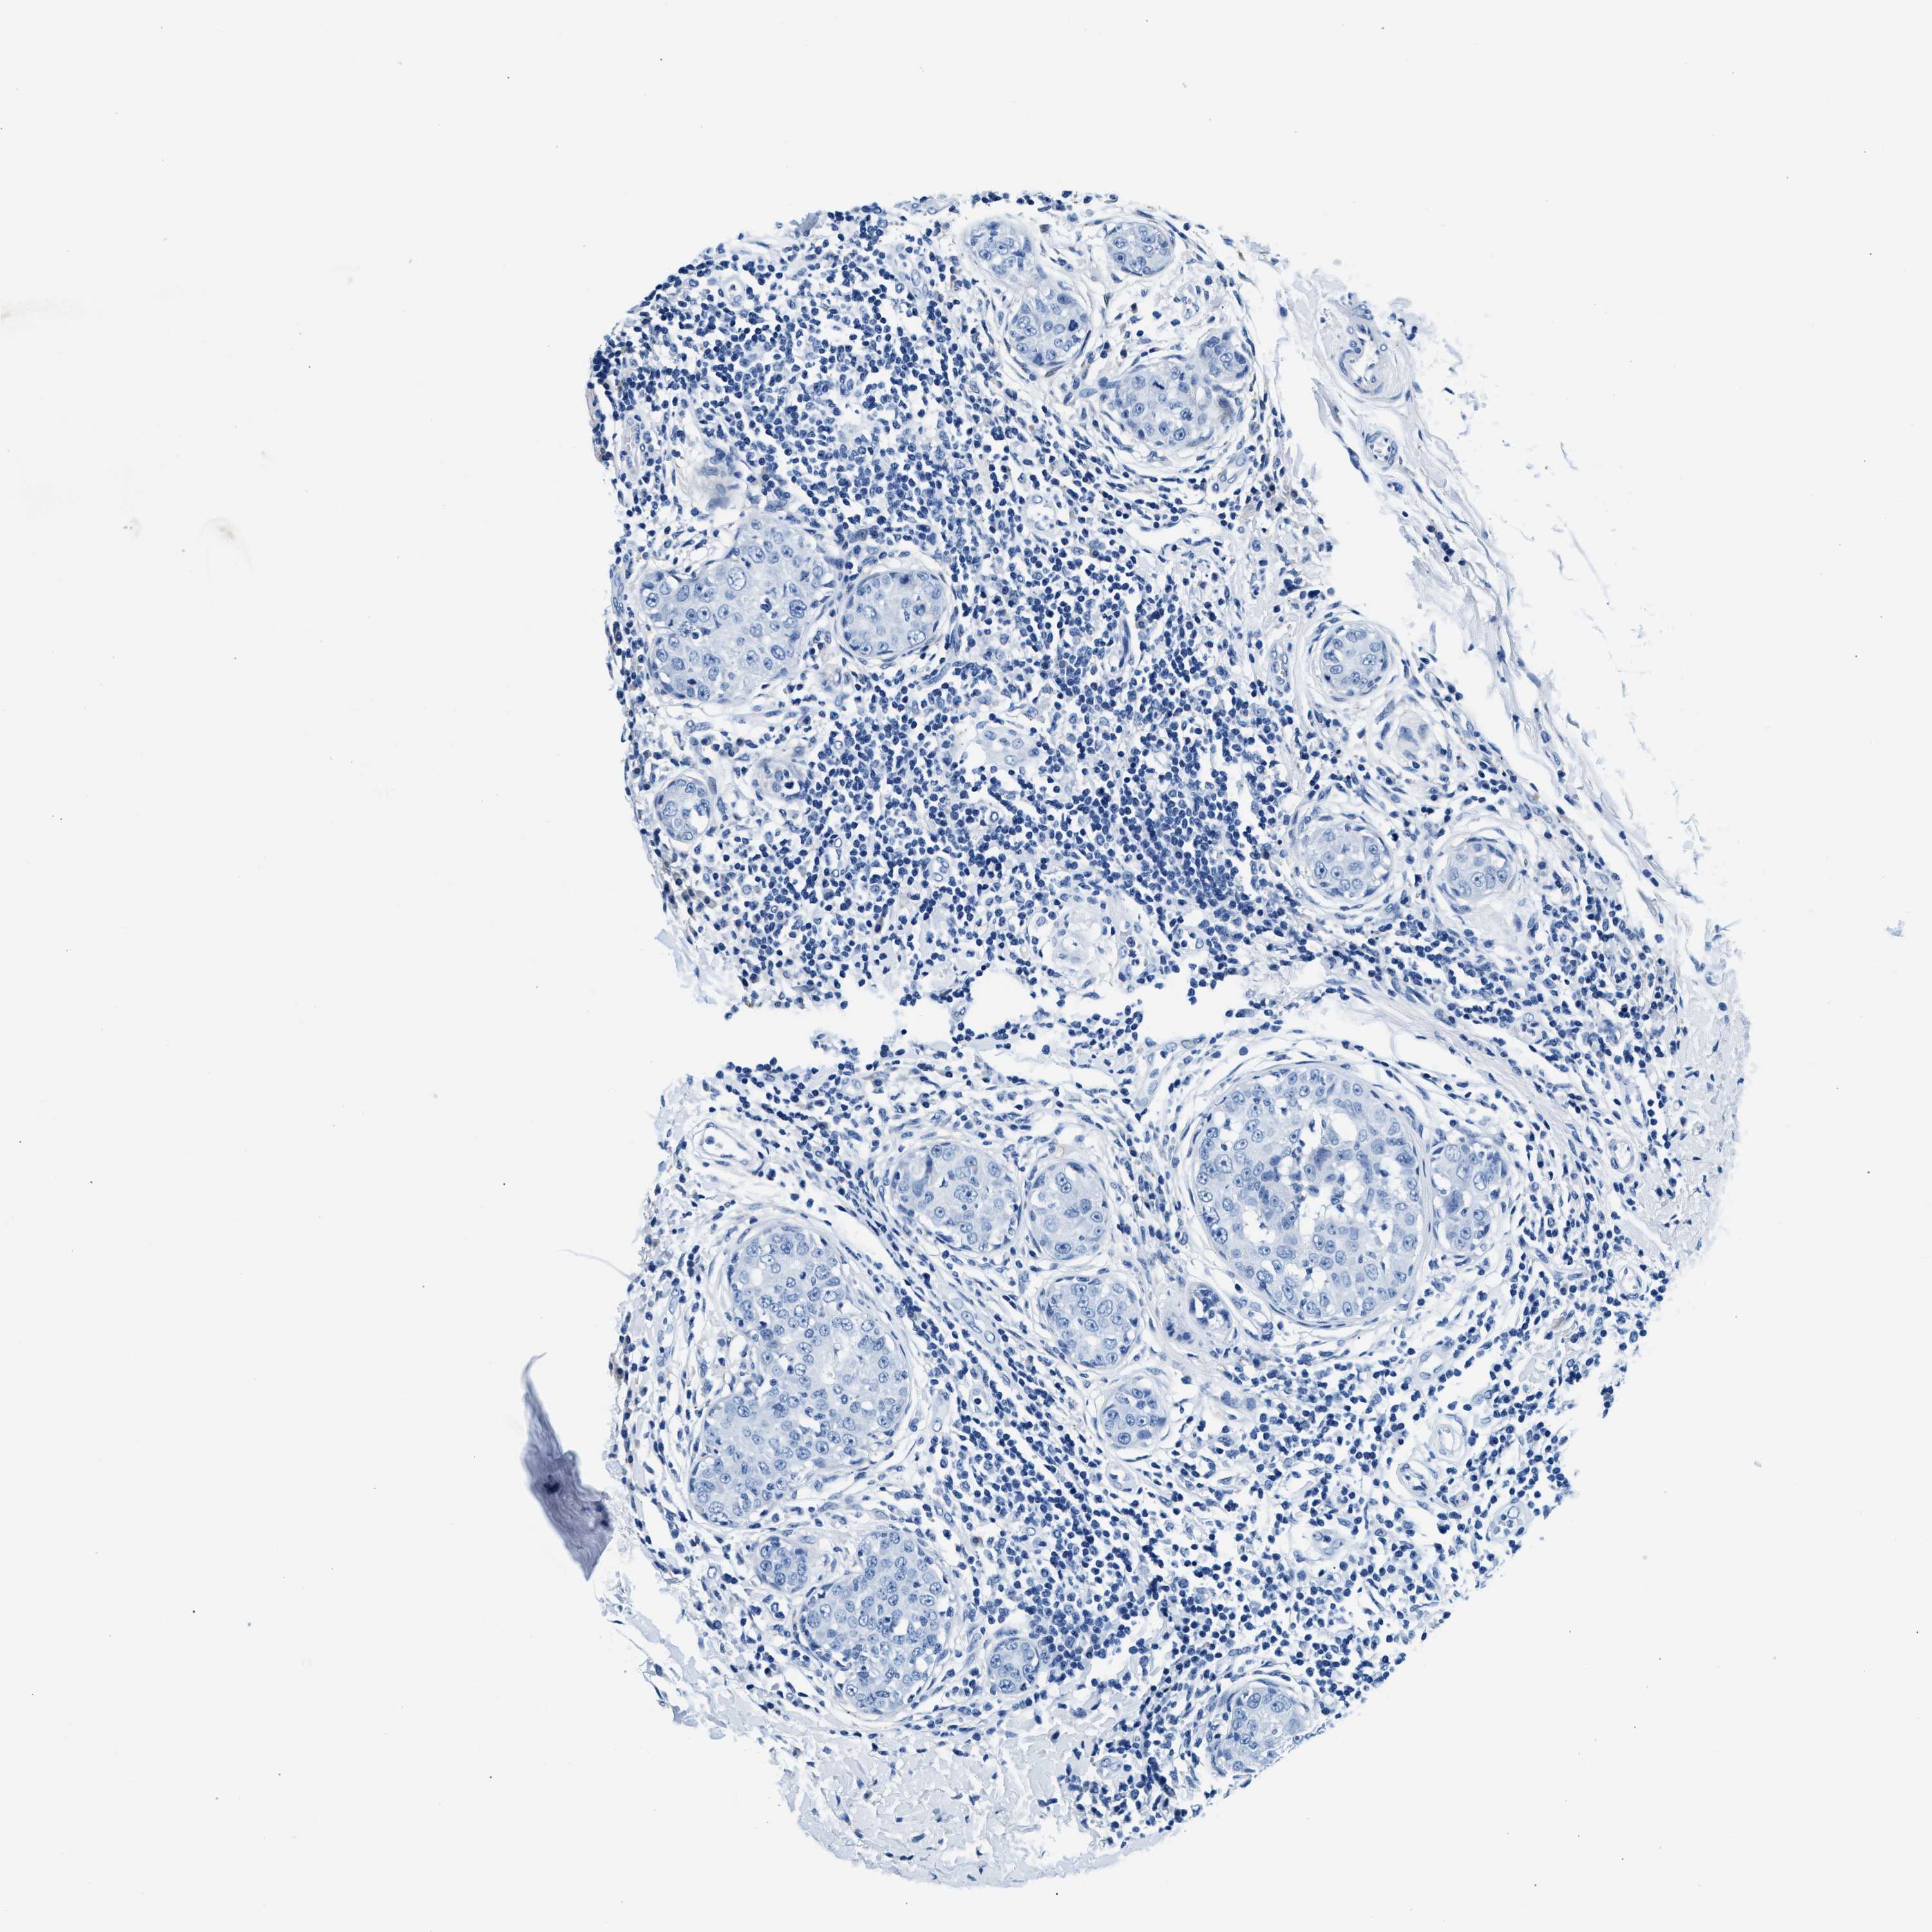

CANCER BREAST CANCER Show tissue menu

BRCA TCGA BRCA VALIDATION PROTEIN EXPRESSION